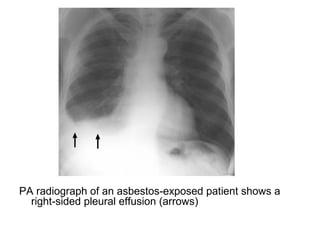

PA radiograph of an asbestos-exposed patient shows a

right-sided pleural effusion (arrows)